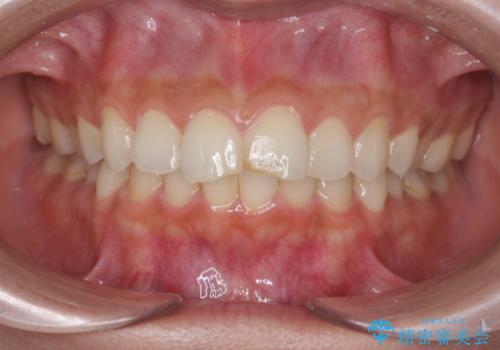

すり減った前歯の形態回復

- すり減ってしまった前歯の審美性の回復を希望され来院されました。

何度かレジン修復を試みたものの、脱離しやすく変色も気になる、とのことでセラミッククラウンによる審美性の回復を計画します。

右側は、クラウンにせず可及的に形態を整えることのみでの対応としました。

自然な色調のセラミッククラウンで審美性を回復することができ、大変満足いただけました。